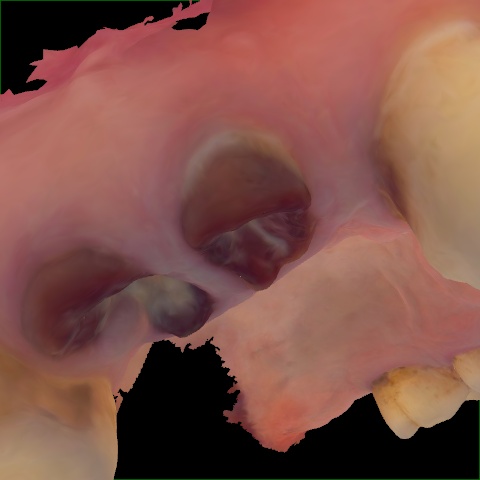

Incorrect Quality Level

The reference annotation for this image is

None

.

Please select the correct quality level.

Annotated as "Good"